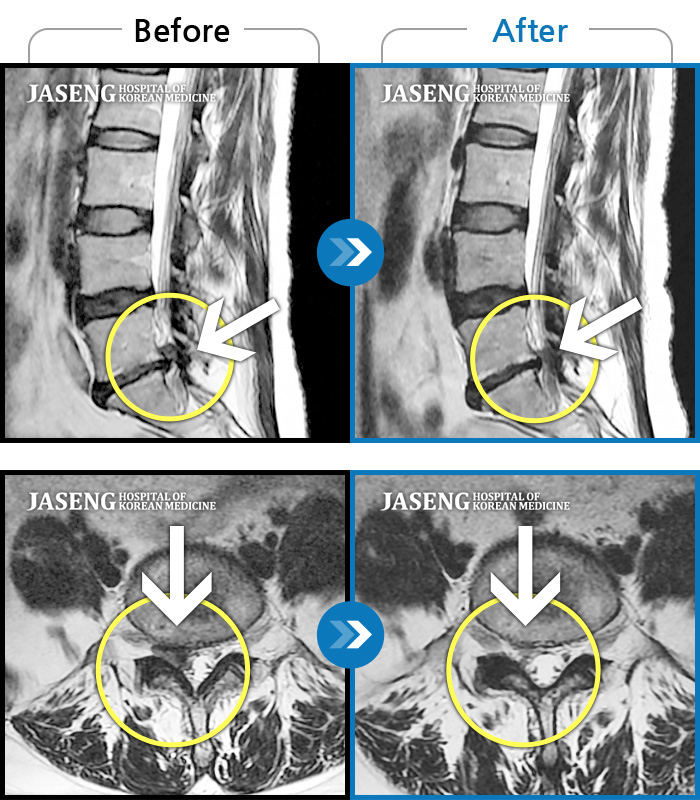

Before

After

환자에게 사전 동의를 받아 동일 조건에서 촬영되었습니다.

개인에 따라 치료 후 부작용이 발생할 수 있으니 의료진과 상담 후 치료를 진행하시기 바랍니다.

내원시 하부 요추 통증으로 보행 불가하고 야간통증

우측 허리 다리 통증으로 야간통, 보행장애